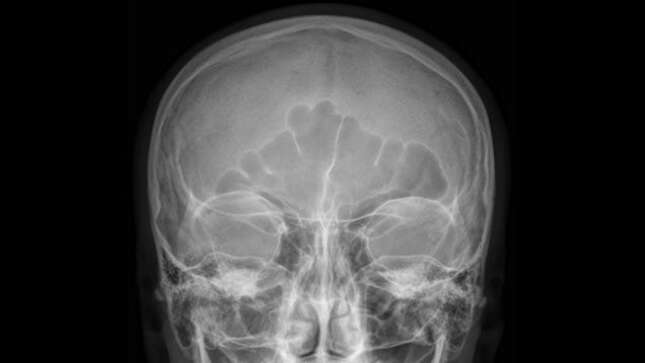

Se trata del “primer caso reportado de un rinolito a base de marihuana que fue adquirido en prisión”. Los rinolitos o cálculos nasales son cuerpos extraños que se calcifican en la cavidad nasal por la acumulación de sales minerales. En este caso, el cuerpo extraño no era un diente que creció mal ni un juguete que un niño se había metido por la nariz, como suele ocurrir, sino “una cápsula de goma que contenía materia vegetal degenerada”. Un globo lleno de marihuana.

Los médicos del Hospital Westmead, en Sídney, usaron anestesia general para extraer el objeto, que se había convertido en un cálculo gris de 19 milímetros. A los tres meses, el hombre se había recuperado de todos los síntomas sinonasales que le habían acompañado durante casi dos décadas.